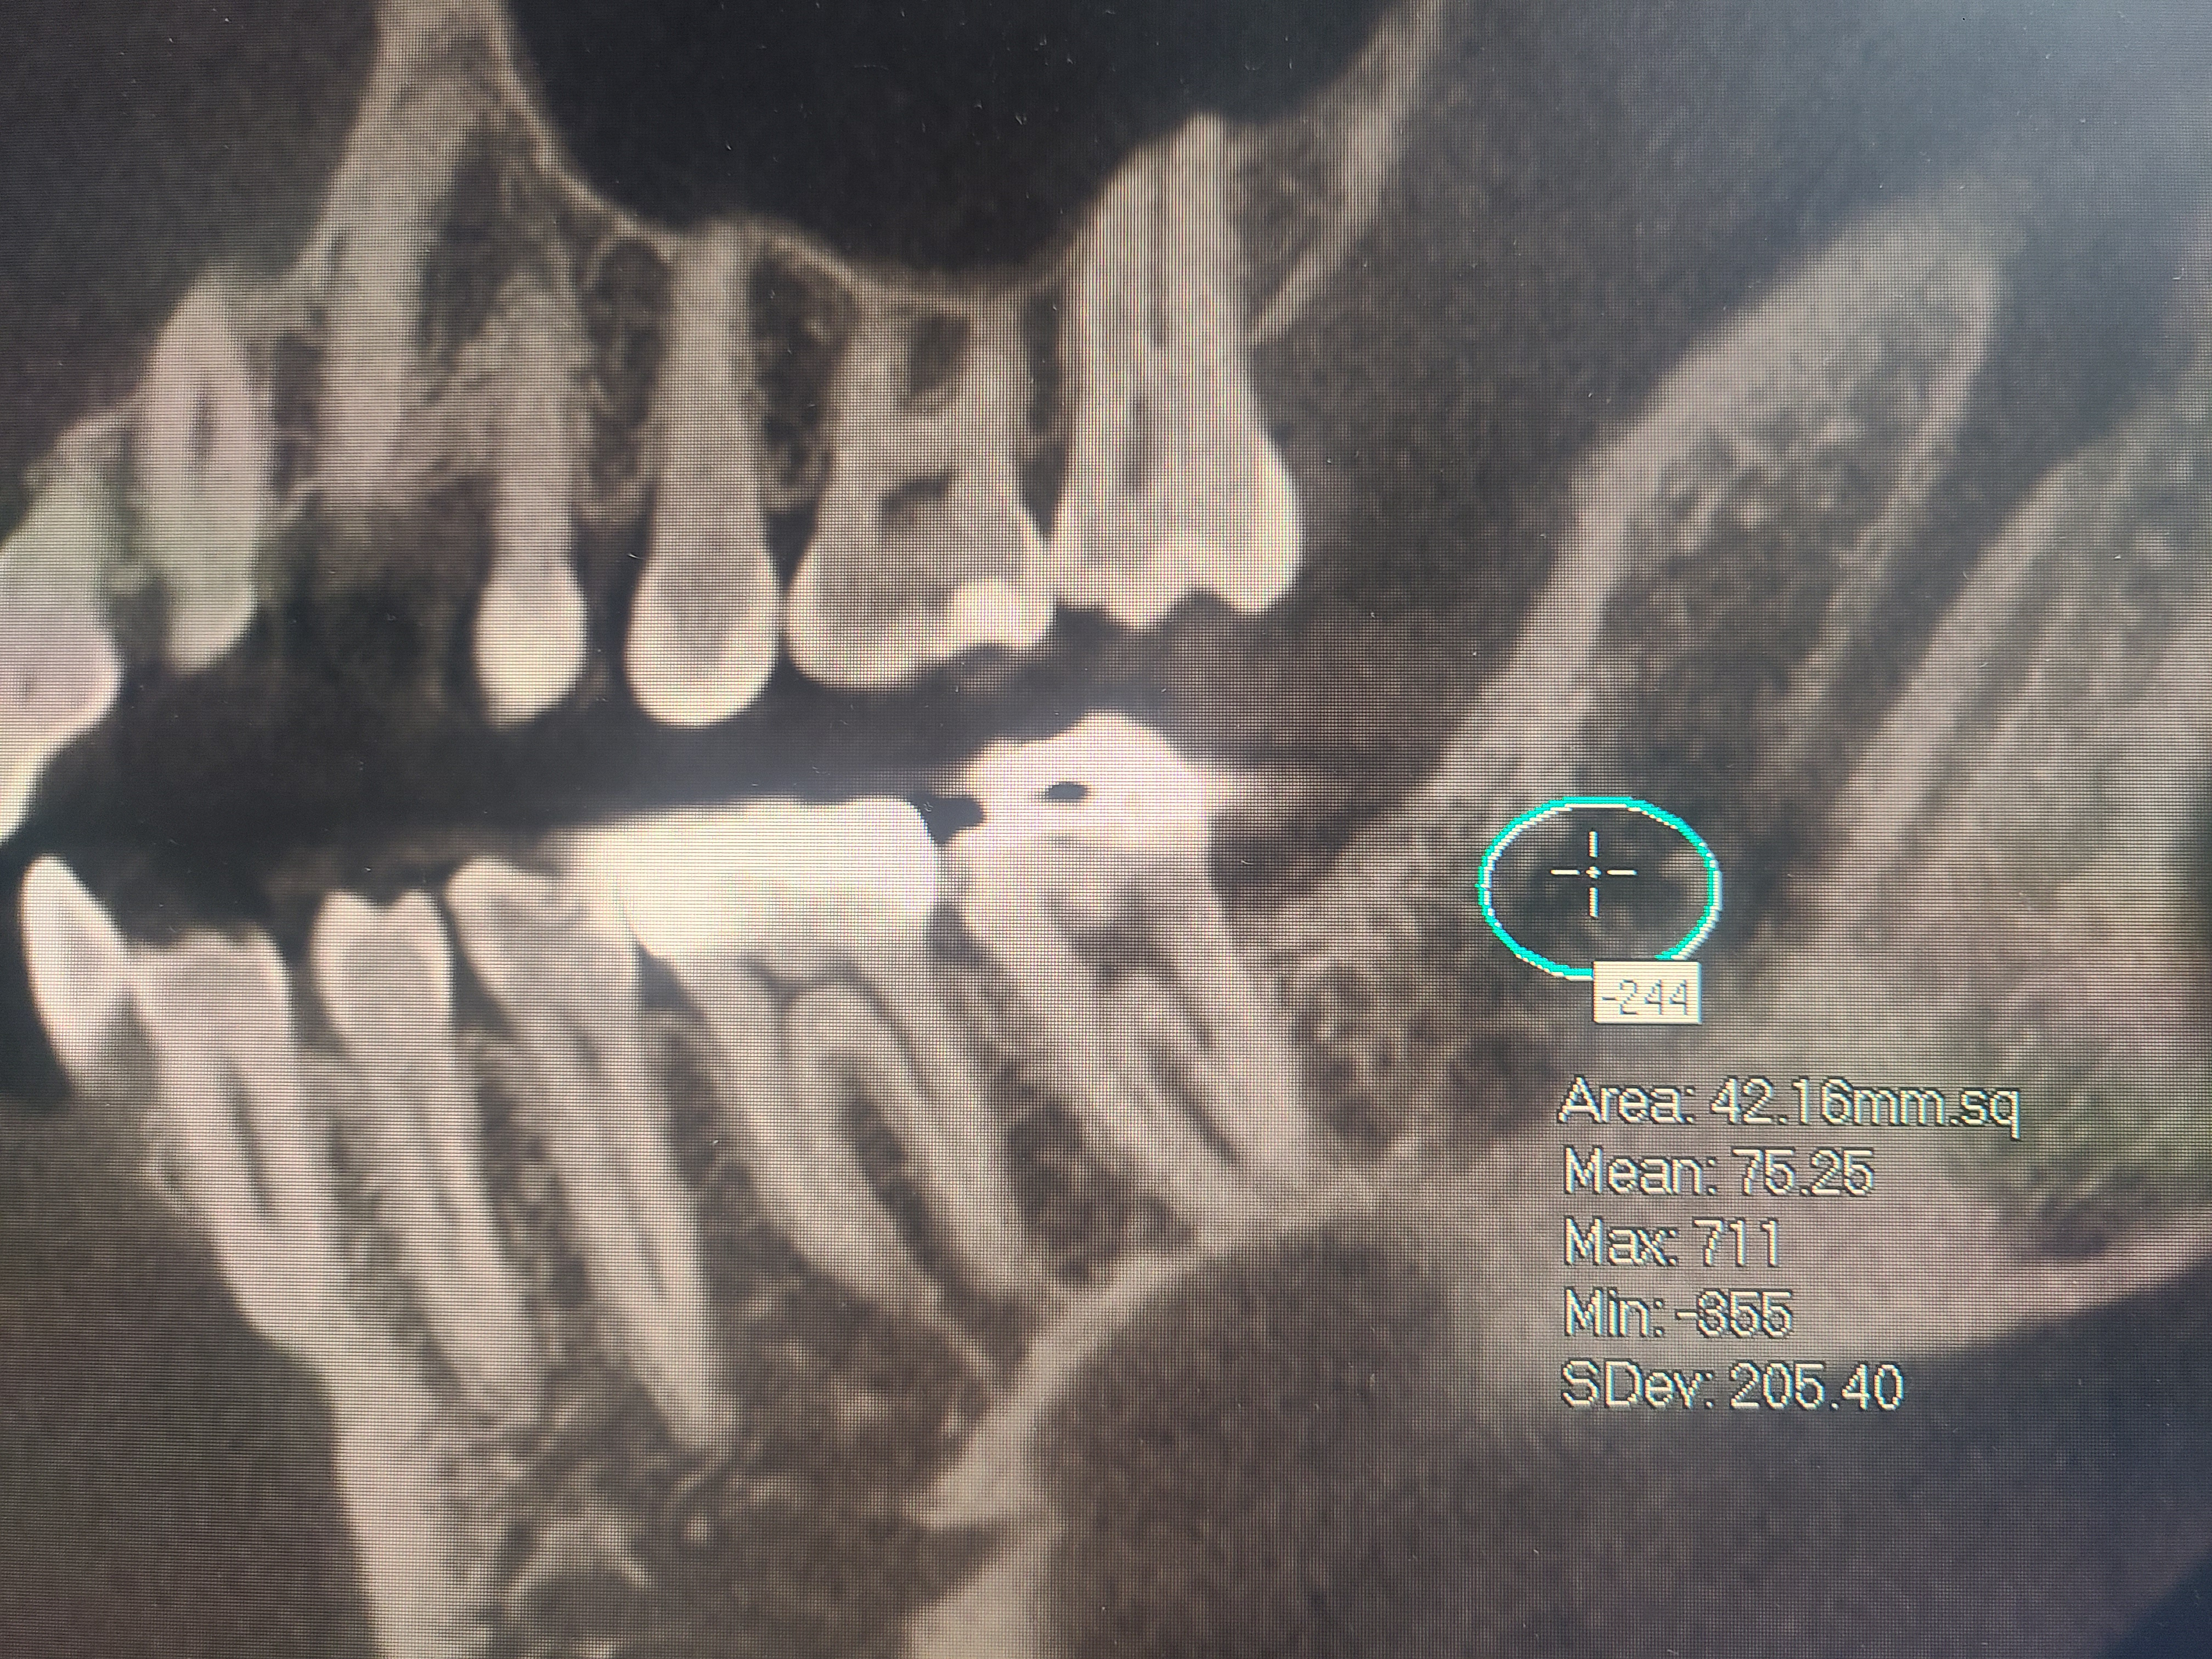

Bone cavitations could be tricky to diagnose, a simple x-ray or panoramic x-ray will not be enough. The best way to diagnose a bone cavitation is with a CT Scan or Cone Beam CT. There are specific CT Scans that can measure bone density. Bone density should not have a negative number. Readings of a (-100) or more are indicators of bone cavitation. They are usually located at extraction sites. For more information, do not hesitate to schedule a consultation with us. We would be honored to have you.